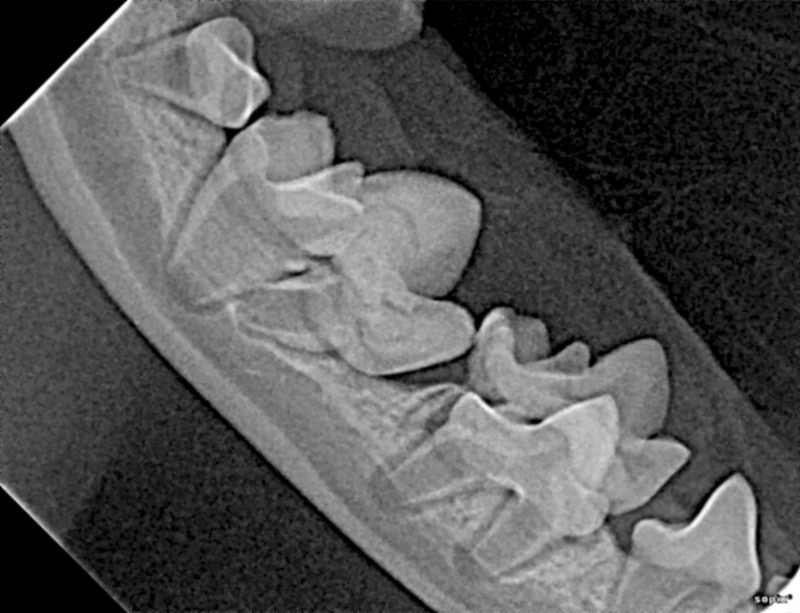

Cone Beam Computed Tomography

The Center now provides advanced imaging via cone beam CT. Cone beam CT is excellent for visualization of bony structures of the skull, nasal cavity, teeth, and ears. Cone beam CT is especially helpful for diagnosing dental disease and evaluation of jaw fractures. It can also be useful for evaluating the sinuses and tympanic bulla. Cone beam CT can be used in conjunction with nasal biopsy and culture to evaluate nasal discharge whether chronic or acute.

Repair of Maxillofacial Fracture

Pets can be involved in trauma that can cause fractures to their head, teeth, and jaw bones. Correctly repairing these fractures is extremely important for your pet to have normal function of their mouth. If a jaw fracture is allowed to heal in an abnormal position, your pet may have great difficulty chewing and can be in significant pain. Many fractures can be successfully treated with minimally invasive oral procedures, but more complicated cases may require bone plating techniques. The Center offers cone beam CT imaging which provides extremely detailed images of the bones of the head and skull. Advanced imaging with CBCT facilitates selection of the best surgical technique to get your pet back to eating and comfort as soon as possible.